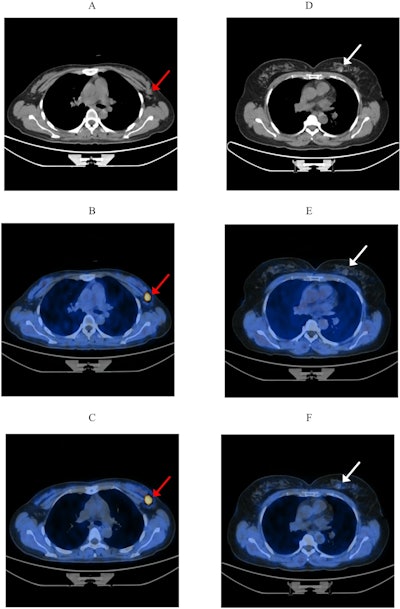

The characteristic imaging features of high-risk breast lesions on early and late F-18 FAPI-04 PET/CT. (A, D) are CT images; (B, E) are early imaging fused images; (C, F) are late imaging fused images. (A–C) A 35-year-old patient diagnosed with invasive ductal carcinoma, as indicated by the red arrow, with ultrasound findings classified as BI-RADS 4a. In the early and late imaging, the maximum standard uptake value (SUVmax) (12.5 vs. 14.2), lesion-to-background ratio (LBR) (22.2 vs. 22.2), respectively. (D–F) A 51-year-old patient with a breast fibroadenoma, as indicated by the white arrow, also categorized as BI-RADS 4a. In the early and late imaging, the SUVmax (0.5 vs. 1.1), LBR (2.2 vs. 2.6), respectively. These findings demonstrate that both SUVmax and LBR in breast cancer are markedly higher than those in benign breast lesions across both imaging phases.The characteristic imaging features of high-risk breast lesions on early and late F-18 FAPI-04 PET/CT. (A, D) are CT images; (B, E) are early imaging fused images; (C, F) are late imaging fused images. (A–C) A 35-year-old patient diagnosed with invasive ductal carcinoma, as indicated by the red arrow, with ultrasound findings classified as BI-RADS 4a. In the early and late imaging, the maximum standard uptake value (SUVmax) (12.5 vs. 14.2), lesion-to-background ratio (LBR) (22.2 vs. 22.2), respectively. (D–F) A 51-year-old patient with a breast fibroadenoma, as indicated by the white arrow, also categorized as BI-RADS 4a. In the early and late imaging, the SUVmax (0.5 vs. 1.1), LBR (2.2 vs. 2.6), respectively. These findings demonstrate that both SUVmax and LBR in breast cancer are markedly higher than those in benign breast lesions across both imaging phases.Scientific ReportsThe results showed a significant difference in SUVmax between early and late imaging (p = 0.001), with F-18 FAPI-04 uptake in the breast cancer group significantly higher than in the benign breast lesion group. The cutoff values for SUVmax were 3.6 for early imaging and 4.1 for late imaging.